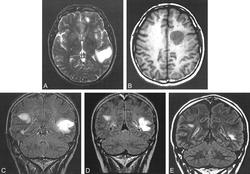

С внедрением в клиническую практику методов нейровизуализации головного мозга (в частности, магнитнорезонансной томографии) появилась возможность прижизненной диагностики КСБ. При проведении МРТ в Т2Wрежиме у больных с КСБ в сером и белом веществе головного мозга выявляются гиперинтенсивные очаги различного диаметра, часть из которых окружена гипоинтенсивными концентрическими кольцами. Взаимосвязь между РС и КСБ подтверждают данные C. Wang и соавт., которые при проведении МРТ в динамике у 7 больных с КСБ наблюдали появление новых очагов демиелинизации, характерных для обоих заболеваний.